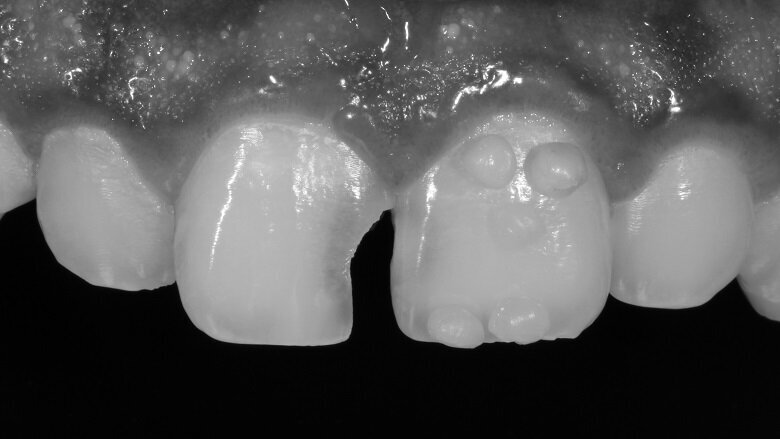

The ultimate blend of value shade can give almost life like and undetectable restorations. A photograph was taken in monochrome mode to depict the value of the tooth (Fig 5).

Fig 5: Monochrome image to depict value